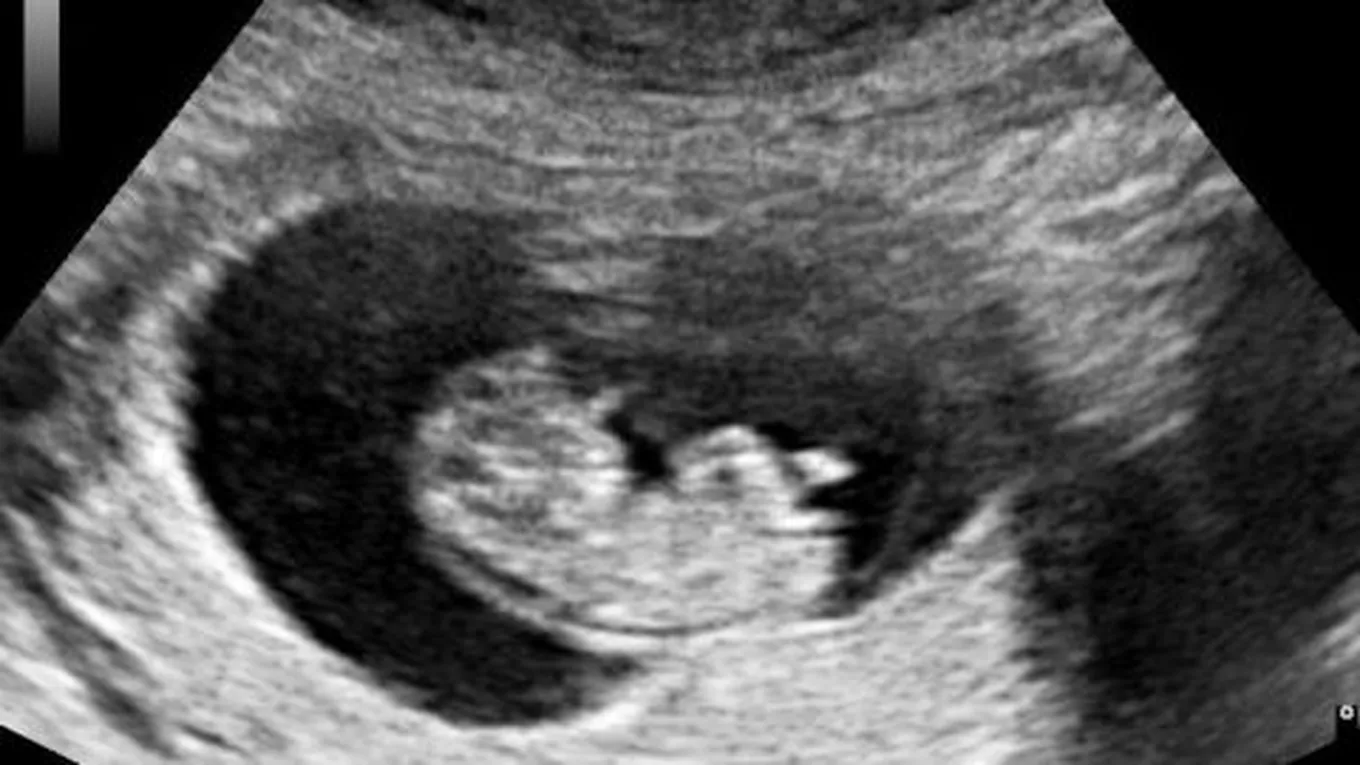

- إجراء فحص ثلاثي أو رباعي الأبعاد باستخدام الموجات فوق الصوتية في الأسبوع الثالث عشر من الحمل.

- إجراء فحص رباعي الأبعاد في الشهر الخامس لتفحص أعضاء الجنين.